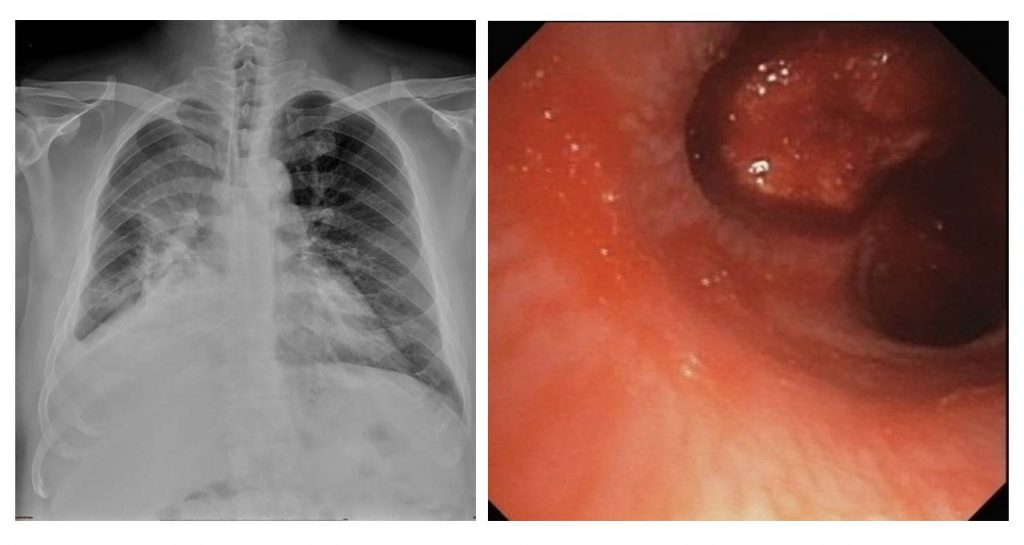

左圖/右上腫瘤X光片:胸部X光顯示右側腫瘤造成右肺塌陷

右圖/右支氣管腫瘤,腫瘤幾乎完全阻塞右側主支氣管,並且有出血的情形

王先生和醫師及家人討論後,接受支氣管鏡檢查。在支氣管鏡鏡頭下,清楚見到一個腫瘤堵住右側主支氣管的通路,並有出血的情形,解釋了為什麼王先生這半年來感覺喘及咳血。醫師切片後替王先生止血,檢查順利結束,病理報告證實為非小細胞肺癌。現今肺癌治療選擇及成效皆較以往大幅進步,王先生也勇敢接受下一步的治療。